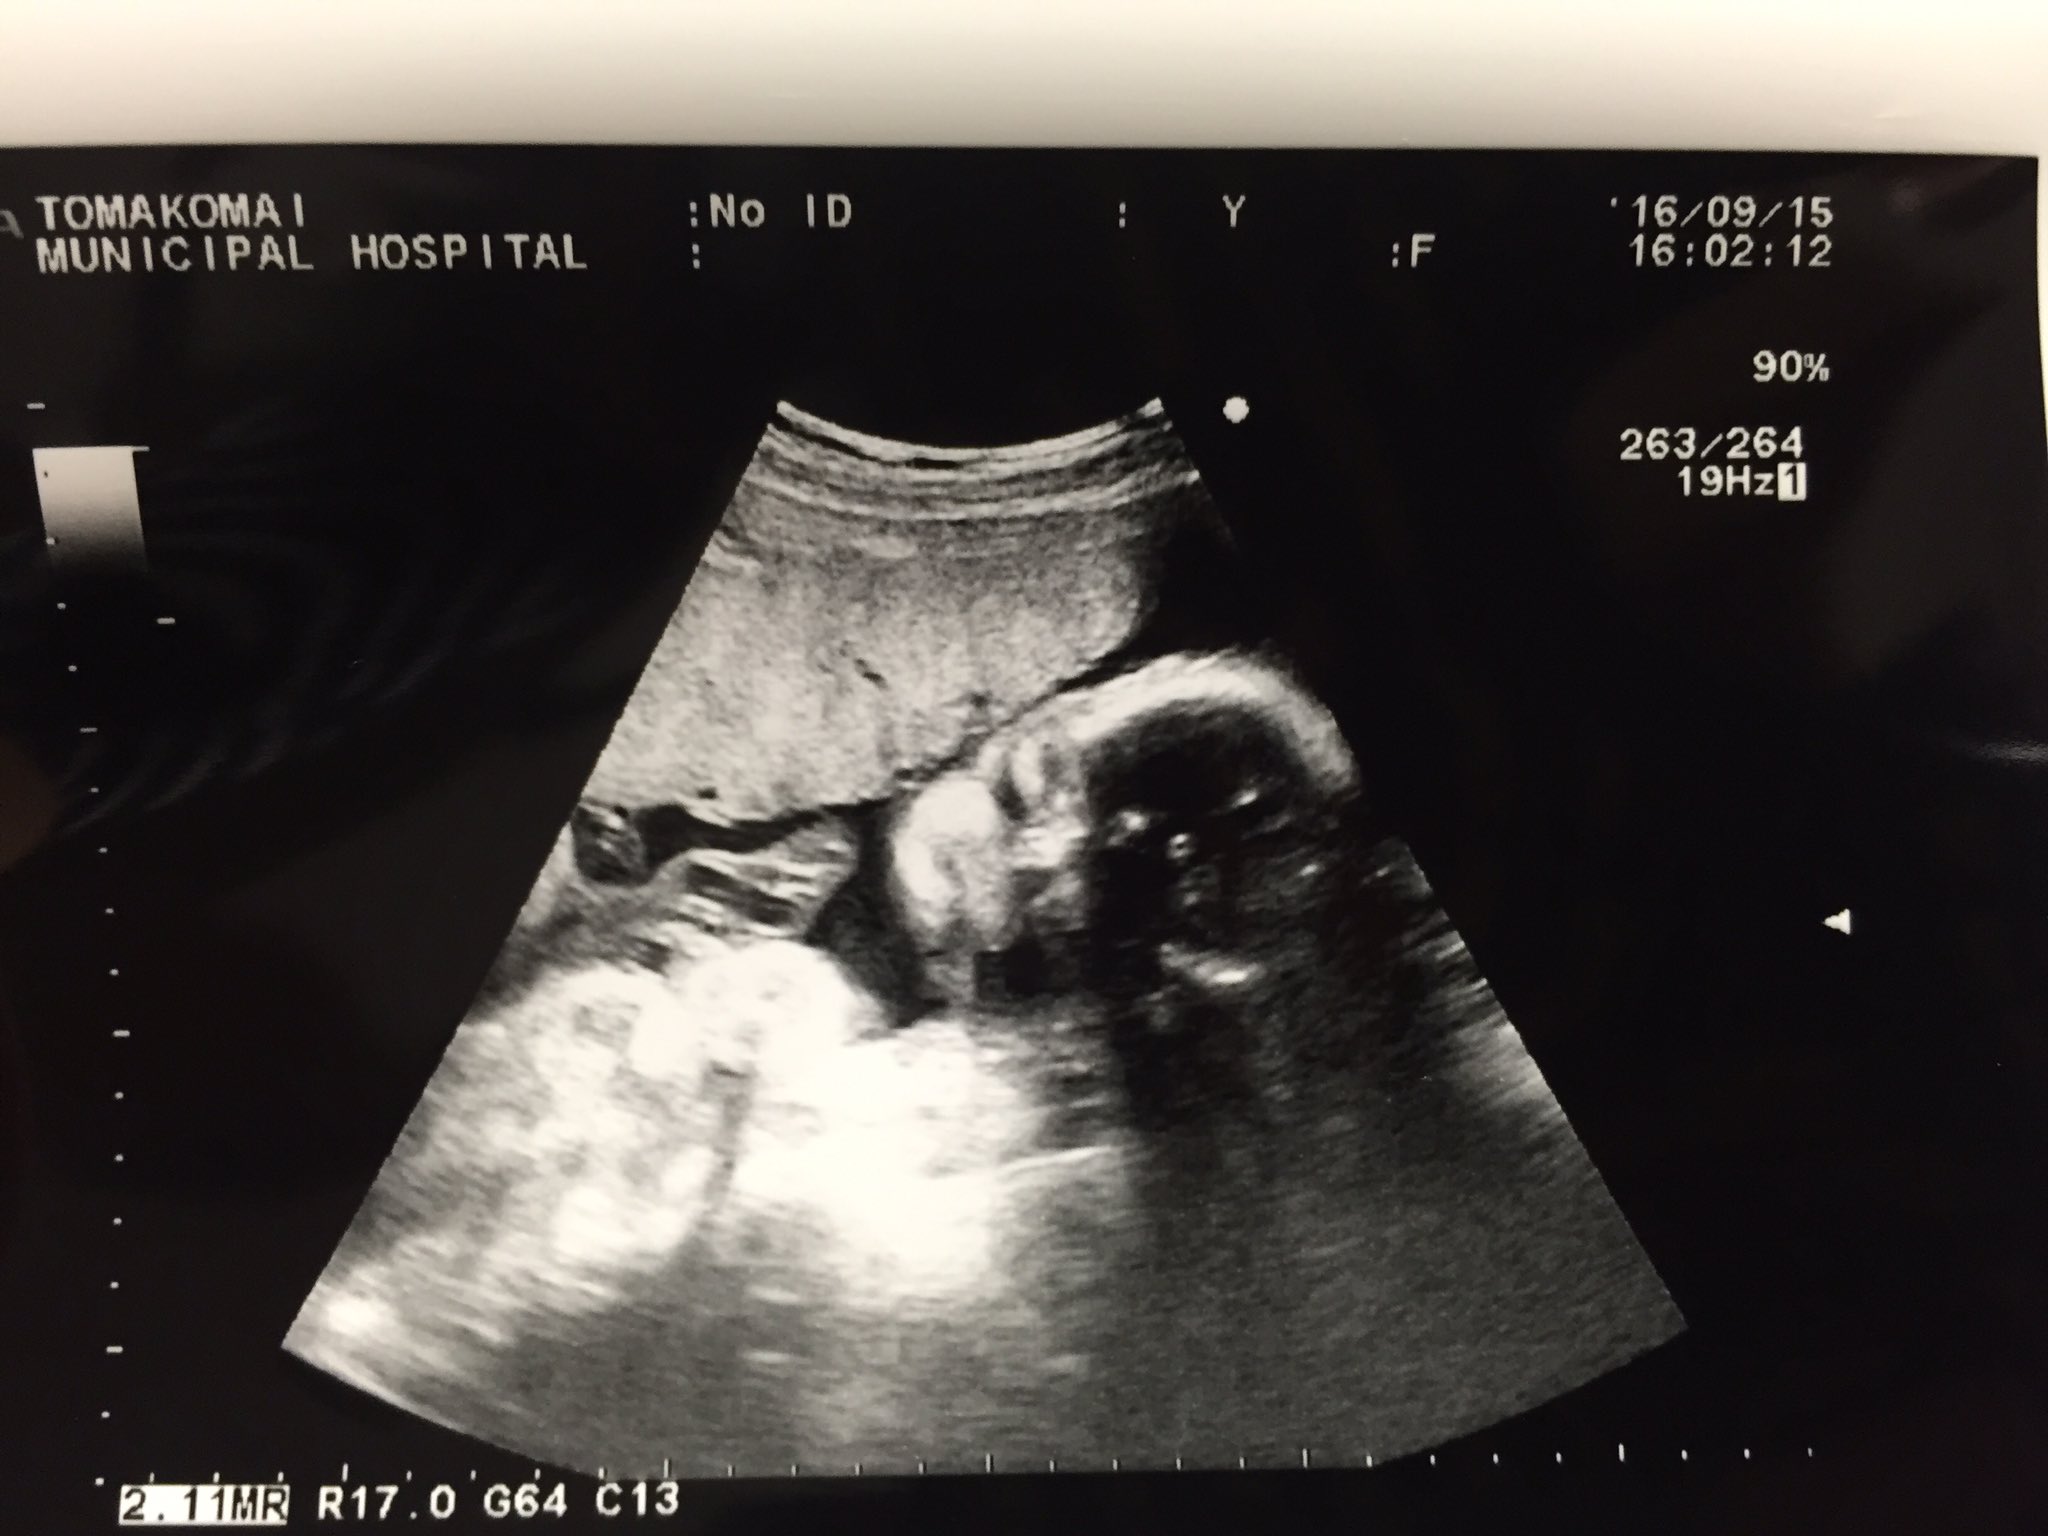

胎児って、あくびしますか・・? この前の27週の検診で、赤ちゃんがものすごく 大きく口を開けて、あくびしているのが見えたのですが、 (看護婦さんも「アクビしているね~」と言いましたが・・) でも、羊水の中にいて、あくびなんて出るものでしょうか?妊娠週 33w5d 33w5d 頭785㎜ おなか290㎜ 大腿骨61㎜ 1970g。 今回は胎児スクリーニング。 赤ちゃんの臓器に異常がないか調べてくれます。 あくびをしている赤ちゃんが見れました♪ (*^^*) 出血もまだ時々あるので心配が絶えませんが赤ちゃんは元気なので

1512/1 28week 1Day Echo Ultrasound 8month※後半に重要な追記あり!赤ちゃんの超音波検査を記録した動画(4倍速)です。前回の検診に引き続き、4D赤ちゃんはあくびもよくしています。赤ちゃんの肺は肺胞液という液体で満たされているので、あくびをして羊水を飲んでも大丈夫♪ 妊娠後期29週 従来のエコーが格段に進化した検査装置で、静止画像ではなく、立体像が動画で見ることができ2Dエコーとは違って、体の内部ははっきり見えません。 4Dエコー(動画、赤ちゃんの動く様子を観察) 3Dエコーに時間の要素を加えて、動画にしたものが「 4Dエコー 」です。 赤ちゃんの表情や動く様子がリアルタイムに観察できます。 妊娠週を過ぎる

4dエコーは映像として映し出されるもので、赤ちゃんの動作を見ることができます。 あくびをする様子や、手を動かしているなどの仕草まで見ることができます。 3d/4dエコーのタイミング 3d/4dエコーのタイミングとしては妊娠週数15~32くらいが良いでしょう。 新生児 画像あり赤ちゃんのエコーが写真と、産まれた後の顔を比べてみると・・・全然似てない! ? 年4月18日 赤ちゃんのエコー写真を見ると、産まれてくる赤ちゃんの顔が見れるので幸せな気持ちになりますよね。 私も出産前は、5Dや6Dエコー